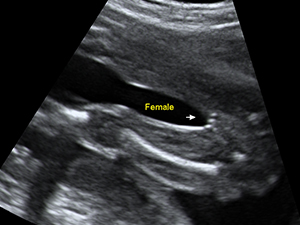

Female genital organ (arrow) at 20 weeks